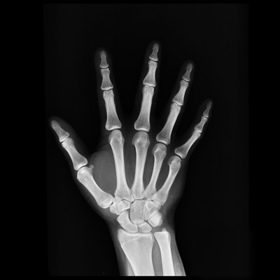

After testing our proposed method on several synthetic images, we now consider applying it on real medical images. Here, we consider a hand X-ray image as the source image (Fig. 7(a)) and a deformed hand X-ray image as the target image (Fig. 7(b)). Fig. 7(c) shows the original absolute intensity difference between the two images. It can be observed that different fingers are displaced in a nonuniform manner (for example, the displacement of the index finger is much larger than that of the little finger), while the wrist remains almost the same. Therefore, a simple rigid transformation is insufficient for yielding a good registration. As shown in Fig. 7(d), our proposed method successfully deforms the source image to match the target image, and the final intensity difference is significantly smaller (see Fig. 7(e)). From the deformed underlying grid in Fig. 7(f), it can be observed that the mapping is smooth and bijective. For comparison, both LDDMM [5] and DDemons [47] fail to register the fingers and are non-bijective (see Fig. 7(g), Fig. 7(h), and Fig. 7(i)).